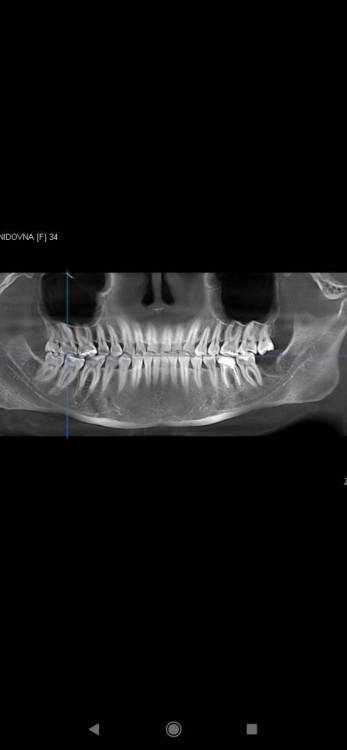

Котенька Опубликовано 24 сентября, 2023 Автор Поделиться Опубликовано 24 сентября, 2023 (изменено) 6 часов назад, red_butler сказал: Здравствуйте, что значит частая замена коронки? В общем,у меня следующая ситуация. Почти год назад на нижнюю шестерку мне установили культевую вкладку и металлокерамическую коронку,которую ортопед сразу установил на постоянный цемент,в итоге она совсем не подошла мне-сильно завышала после подпиливания эмали коронки до металла.Врач снял неудачную коронку и установил по гарантии новую,отправив неделю привыкать к ней.Контактные пункты коронки с соседними зубами были хорошие.Но всё же мешались бугорки и я отправилась на корректировку.Врач подпилил мне ее и в итоге контактный пункт между коронкой и седьмым зубом стал не очень плотным-стала забиваться еда и поднывать десна.Ортопед сказал,что с контактным пунктом все хорошо и десна там нормальная,рекомендовал пользоваться ирригатором и если проблема останется,что-нибудь сделаем.Но пародонтолог в другой клинике сказала мне,что проблема есть,другой врач тоже подтвердил,что контактный пункт не очень плотный. После установки коронки я посещала другую клинику,где мне сказали,что,скорее всего,мне нужно ставить брекеты из-за скученности(при этом,возможно,снять коронку и установить временную,если брекет не закрепится на керамику) и/или завысить прикус постановкой керамических накладок на все 6,7 зубы и, соответственно,коронку на 6 зубе всё равно нужно будет менять в таком случае под новый прикус.Также врач сказал,что пока могу ходить в своем прикусе,просто на ночь носить капу от стираемости. Сейчас,пока гарантия ещё не закончилась,пойду к первому ортопеду,тк очищение ирригатором не помогает устранить проблему.Возможно,предложит замену коронки и при этом мне "светят" замены коронки из-за брекетов или накладок.Но я не знаю,когда я на это решусь и пока хочется устранить проблему с застреванием пищи.Какой оптимальный выход в моей ситуации? Боюсь,что частой заменой коронок при наличии вкладки убью зуб окончательно и нужен будет имплант. Извините,если напутано написала-я уже устала от этих переживаний. Изменено 24 сентября, 2023 пользователем Котенька Ссылка на комментарий

Котенька Опубликовано 24 сентября, 2023 Автор Поделиться Опубликовано 24 сентября, 2023 7 минут назад, red_butler сказал: Уважаемые пациенты! Данный форум предназначен для оказания он-лайн консультаций пациентам специалистами форума. Специалисты дают консультации по реальным, а не гипотетическим проблемам. Также специалисты не проводят обучения по теоретической и практической стоматологии для пациентов. Если Вы хотите получить максимально информативный ответ максимально быстро, пожалуйста, соблюдайте следующие правила: 1) В 99% случаев невозможно дать рекомендацию, основываясь только на словах пациента, поэтому обязательно просим прикладывать рентгеновские снимки и фотографии, которые могут помочь докторам разобраться в ситуации. Если Вы просто опишете свою ситуацию, не предоставив снимок, у Вас все равно его попросят, - даже в клинике диагнозы не ставятся только со слов пациентов, не говоря уже об Интернете. Не испытывайте терпение администраторов и отвечающих врачей - СНАЧАЛА СДЕЛАЙТЕ СНИМОК, А ЗАТЕМ ЗАДАЙТЕ ВОПРОС. И еще раз: Со слов пациента диагнозы не ставятся! Отсутствие снимков приведет к закрытию темы! Снимки можно сделать в частной клинике, забрать с собой и разместить в форуме. Если снимки на пленке, то нужно не СКАНИРОВАТЬ, а ФОТОГРАФИРОВАТЬ, как, описано здесь. 2) Кратко и по существу опишите проблему и задайте свой вопрос. ВНИМАНИЕ: открывайте свою собственную тему! Не нужно писать в темах других пациентов, это затруднит поиск Вашего сообщения и приведет к путанице. На форуме много места, поверьте, его хватит всем! В названии темы постарайтесь кратко отразить суть вопроса. Нежелательно называть тему "Помогите!", "Есть вопрос" и т.п., это неинформативно. 3) Пожалуйста, уважайте время докторов. Все профессиональные участники являются практикующими врачами-стоматологами, консультирующими в свое свободное время. Многие и конкретные, и отвлеченные вопросы уже не раз обсуждались за несколько лет существования форума, поэтому если Ваш вопрос не касается Вашей личной ситуации во рту, сначала попробуйте воспользоваться поиском. Темы о том, «какие врачи плохие и жадные», популярности не имеют, как и длинные пространные рассуждения ни о чем. 4) Форум является открытым ресурсом, в нем участвуют доктора со всей России и из других стран. Здесь предлагаются вероятные решения Вашей проблемы на основе предоставленных Вами же данных. Мнения специалистов могут расходиться. Если совет доктора Вас не устраивает, Вы вольны принимать решение самостоятельно. Агрессия и хамство недопустимы, здесь никто никому ничего не должен. 5) Отдельный совет любителям давать советы. Как бы ни хотелось поделиться своим выстраданным опытом, задающие вопрос пациенты прежде всего расчитывают получить ответ от специалиста. Пообщаться и обменяться пациентским опытом можно в «личке» (она же «приват»). Высказывая свое мнение по случаю другого пациента, Вы только вводите в заблуждение его и остальных пациентов, читающих форум. Пациенты! НЕ пишите, пожалуйста, НИЧЕГО в теме других пациентов! 6) Если Вам нужна рекомендация по выбору клиники, в каждом тематическом форуме существует отдельная тема для запроса рекомендаций (не забывайте обязательно указывать город, даже если это Москва). Обратите внимание, что размещение сообщения в теме для рекомендаций не гарантирует ответа врачей. Вы также можете самостоятельно обратиться к понравившемуся доктору в личку. Хорошо,а теоретически частая замена коронки при наличии культевой вкладки может привести к повреждению зуба,корня? Ссылка на комментарий